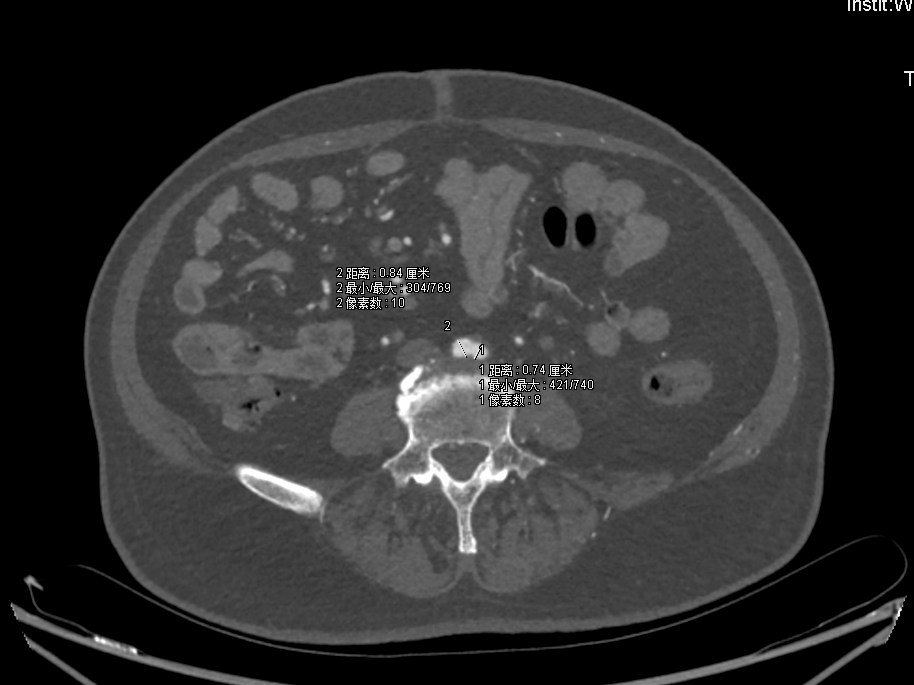

腹主动脉重度狭窄, 多发钙化伴附壁血栓;

RCA=8.4mm,LCA=7.4mm。

ABI:右=0.93,左=0.47;

68岁男性,双下肢间跛4+年多,长期吸烟史,高血压,糖尿病。

查体:左侧足背A(-),左侧股A(-) , 右侧足背A(+),右侧股A(+);